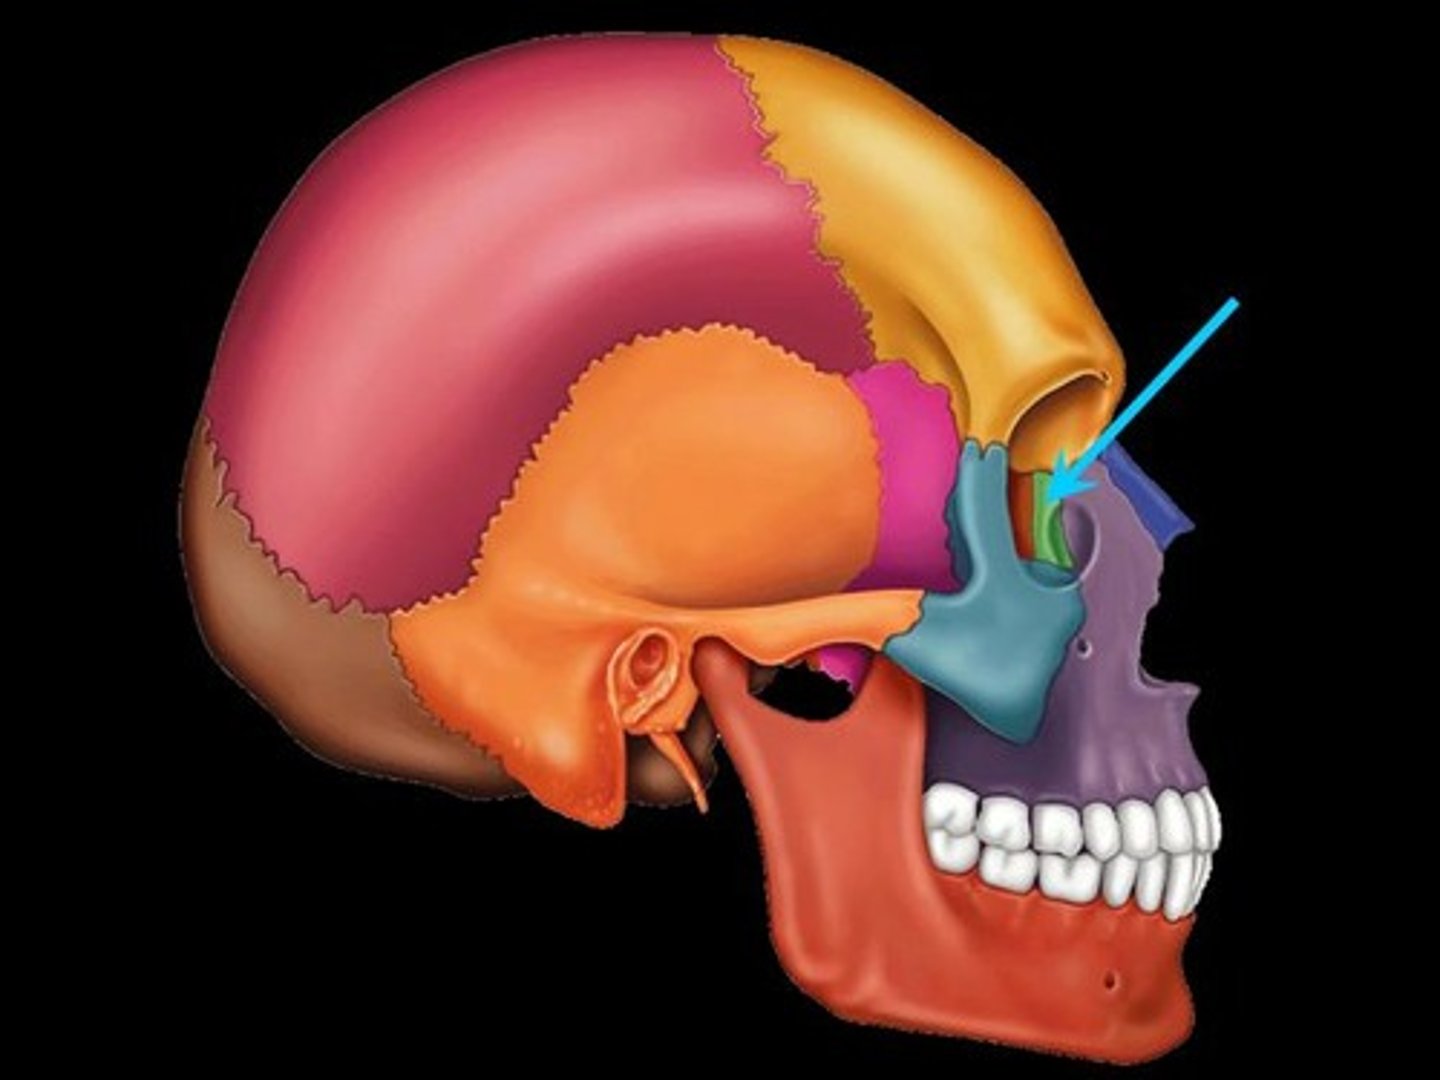

Sphenoid Bone

Forms part of the base of the skull and parts of the floor and sides of the orbit

Superior Orbital Fissure

A foramen in the skull lying between the lesser and greater wings of the sphenoid bone

Inferior Orbital Fissure

An opening in the maxillary bone of the skull located below the infraorbital margin of the orbit. It transmits the infraorbital artery and vein, and the infraorbital nerve, a branch of the maxillary nerve.

Optic Canal

A cylindrical canal running obliquely through the lesser wing of sphenoid bone near the base where it joins the body of sphenoid. It transmits the optic nerve and ophthalmic artery.

Foramen Rotundum

Located at the base of the greater wing of the sphenoid, inferior to the superior orbital fissure. It provides a connection between the middle cranial fossa and the pterygopalatine fossa. The maxillary nerve (branch of the trigeminal nerve, CN V) passes through this foramen.

Foramen Spinosum

The middle meningeal artery, middle meningeal vein, and the meningeal branch of the mandibular nerve pass through the foramen.

Foramen Ovale

An oval shaped opening in the middle cranial fossa located at the posterior base of the greater wing of the sphenoid bone. It transmits the mandibular division of the trigeminal nerve (CN V3) and the accessory meningeal artery.

Sella Turcica

Depression in the sphenoid bone where the pituitary gland is located

Pterygoid Process

Process of the sphenoid bone, consisting of two plates

Zygomatic Bones

The two bones, one on each side of the face, that form the high portion of the cheek

Lacrimal Bones

Small, thin bones located at the front inner wall of the orbits (eye sockets)

Maxilla Bones

The maxilla bones are paired bones joined in the midline. They are located in the upper lip region and together are commonly referred to as the "upper jaw." They also form a portion of the wall of the orbit, the wall of the nasal cavity, the hard palate, and they contain the upper row of teeth.

Palatine Bones

Form the anterior part of the hard palate of the mouth and the floor of the nose